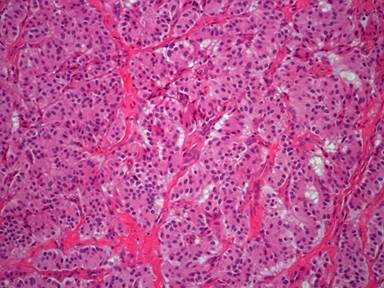

Macroscopically, the pancreatic mass weighted 23 g and measured 23x16x11 mm. The mass was oval-shaped, well-demarcated, soft and pinkish in color. Cut-surface showed tan soft tissue. Microscopically, the uniform intermediate-sized tumor cells were organized in solid trabeculae or nests separated by fibrovascular stroma (Figure 2). The cells had centrally located oval-shaped nuclei, stippled (salt-and-pepper) chromatin and scant finely granular eosinophilic cytoplasm. No evidence of mitosis was identified. Furthermore, there was no evidence of vascular or perineural invasion. Surgical resection margins were tumor-free. Immunohistochemically, tumor cells stained positive for chromogranin A, synaptophysin, insulin and Ki-67 (6%) (Figure 3). Tumor cells stained negative for somatostatin. Based on the clinical, laboratory, imaging, histopathological and immunohistochemical studies, a final diagnosis of benign insulinoma neuroendocrine tumor, World Health Organization (WHO) grade 2, was established.

Figure 2. Microscopic examination of the resected pancreatic mass showing that the tumor cells were organized in solid trabeculae or nests separated by fibrovascular stroma (magnification power, 20x). |